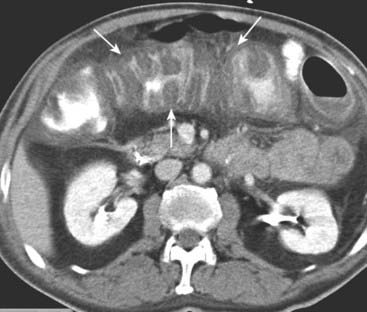

image

Figure 18-12 Crohn disease.

A, The terminal ileum (solid black arrow) is markedly narrowed (string sign) and stands apart from other loops of small bowel (proud loop). B, A close-up image of the right lower quadrant from a small bowel follow-through study in another patient shows multiple streaks of barium (solid and dotted white arrows) representing multiple enteric fistulae originating from an abnormal loop of small bowel (dashed white arrow) and connecting with each other and the large bowel. Fistula formation is a common complication of this disease.